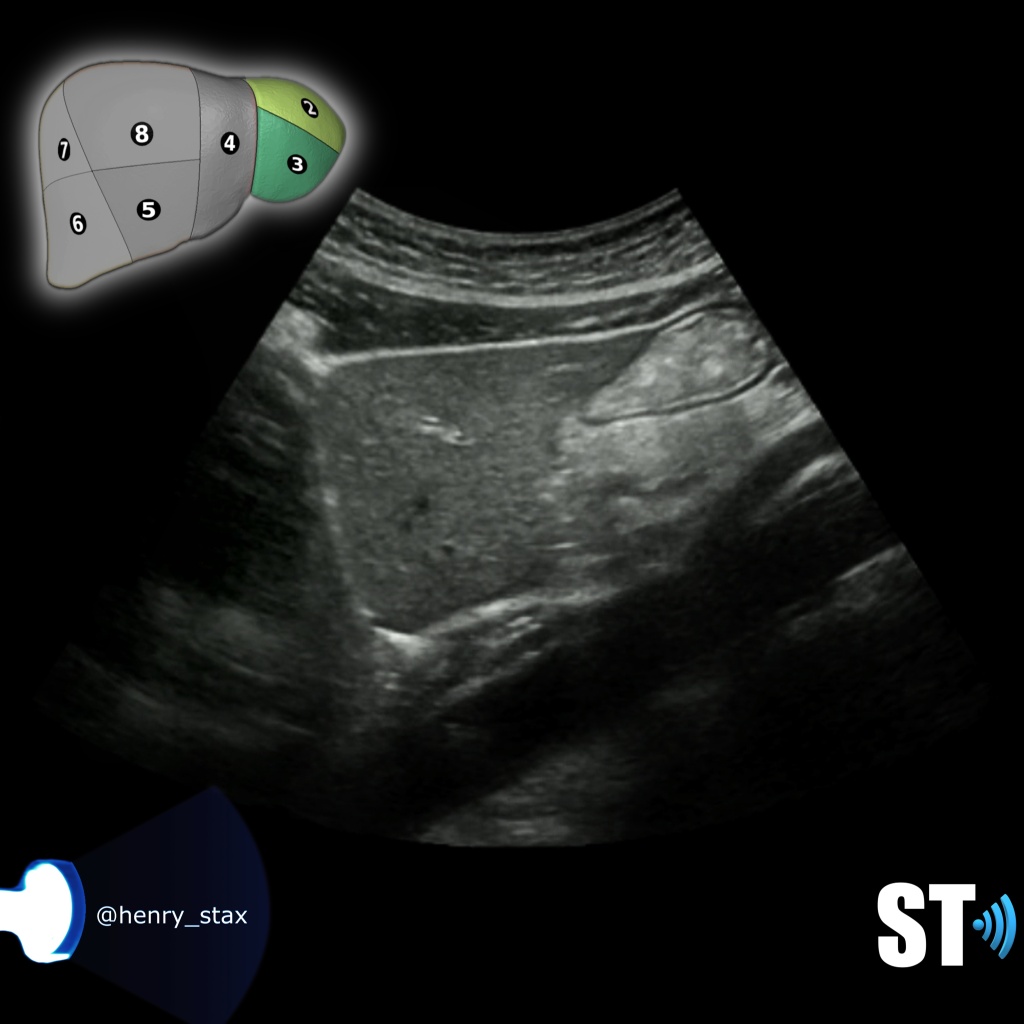

Sagittal

Liver Lt Lobe

Liver Left Lobe segments II and III